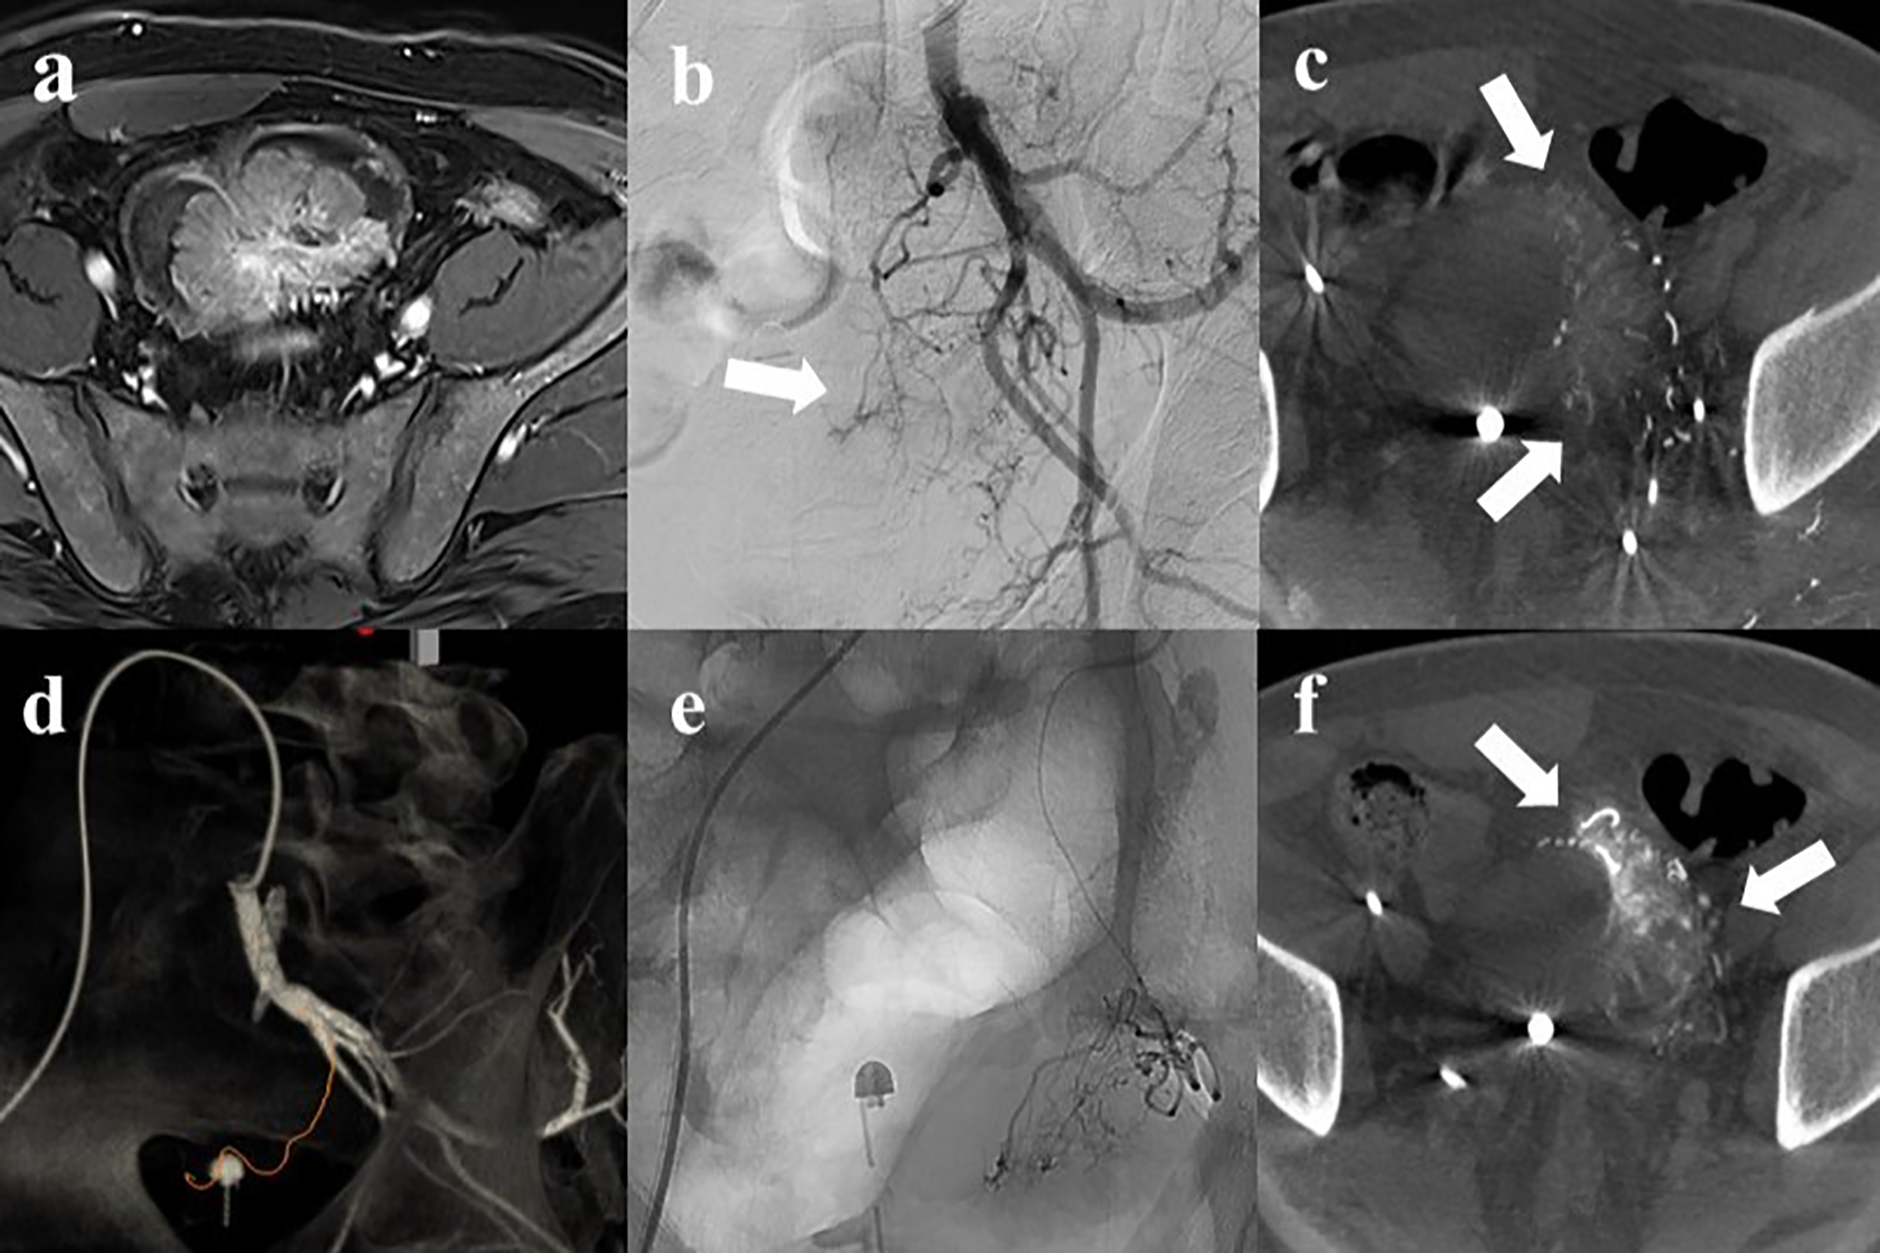

A 53‑year‑old male with intractable hematuria due to bladder cancer. (a) Magnetic resonance imaging revealed a 7 cm enhancing bladder dome mass. (b) Left internal iliac angiography showed hypervascular tumor staining (arrow) with complex vascular anatomy. (c) Axial cone‑beam CT (CBCT) showed perfusion to the left side of the tumor (arrow). (d) Automated feeder detection identified the vessel pathway (red line) leading to the tumor. (e) Superselective embolization was performed using tris‑acryl gelatin microspheres. (f) Post‑embolization CBCT revealed contrast retention (arrow) within the tumor, followed by contralateral embolization using the same protocol.